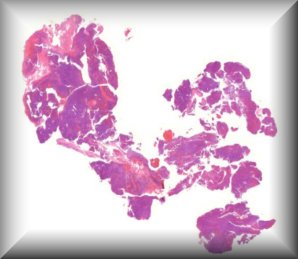

Luis Alfaro: A 65-year-old woman with a rapidly growing tumor in the upper left eyelid |